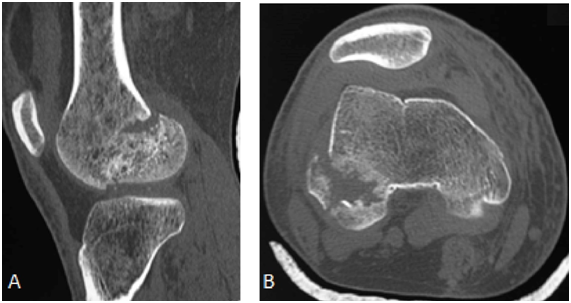

Radiograph of the right knee showed fracture of the posterior aspect of the lateral femoral condyle - Hoffa fracture - type II (Figure 1). CT scan shows fracture of the lateral femoral condyle with a slight misalignment and separation of the fragment, which indicated surgery (Figures 1 & 2). The patient was discharged after surgery, attending since the being accompanied ambulatorially since then (Figure 3).

Figure 1 In A, anteroposterior radiograph and CT scan coronal section in B demonstrating fracture of the lateral femoral condyle with a slight misalignment and separation of the fragment.